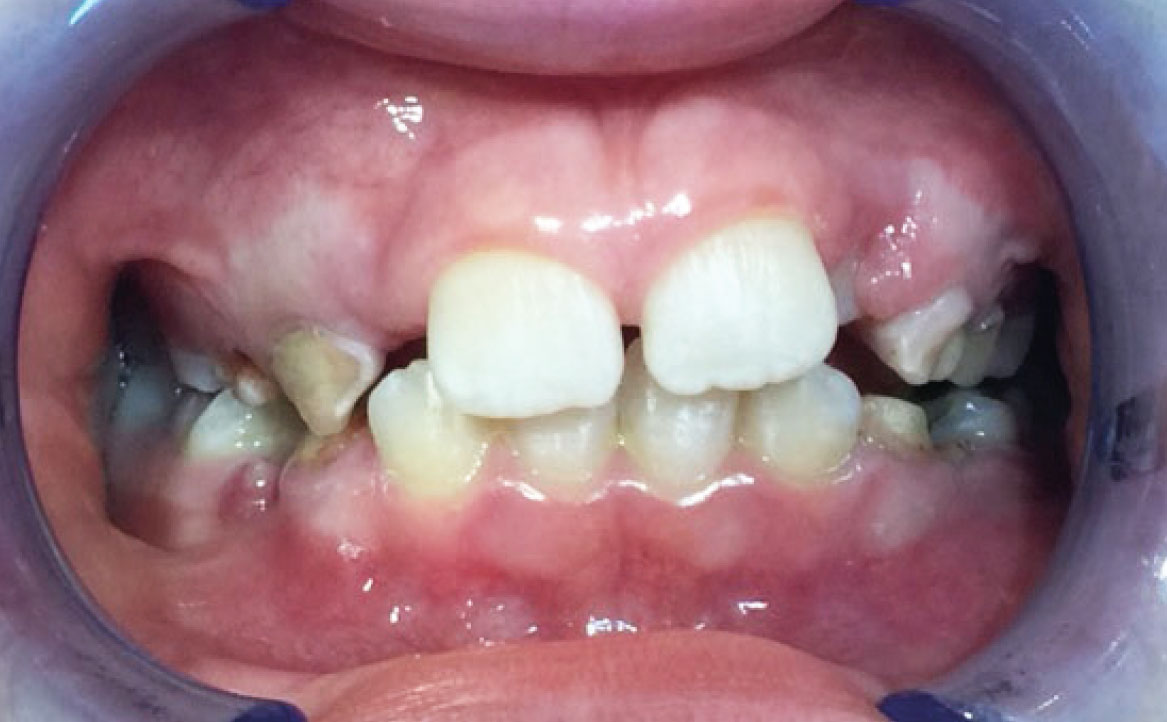

Dall’esame obiettivo intra orale si osservava una seconda classe canina destra e sinistra, una seconda classe molare destra e sinistra, e un diametro inter-canino e inter-molare ridotto sia in riferimento al mascellare superiore sia al mascellare inferiore (fig. 3A-3E).

Clinical examination revealed high caries risk, poor oral hygiene, and constricted upper and lower arches.